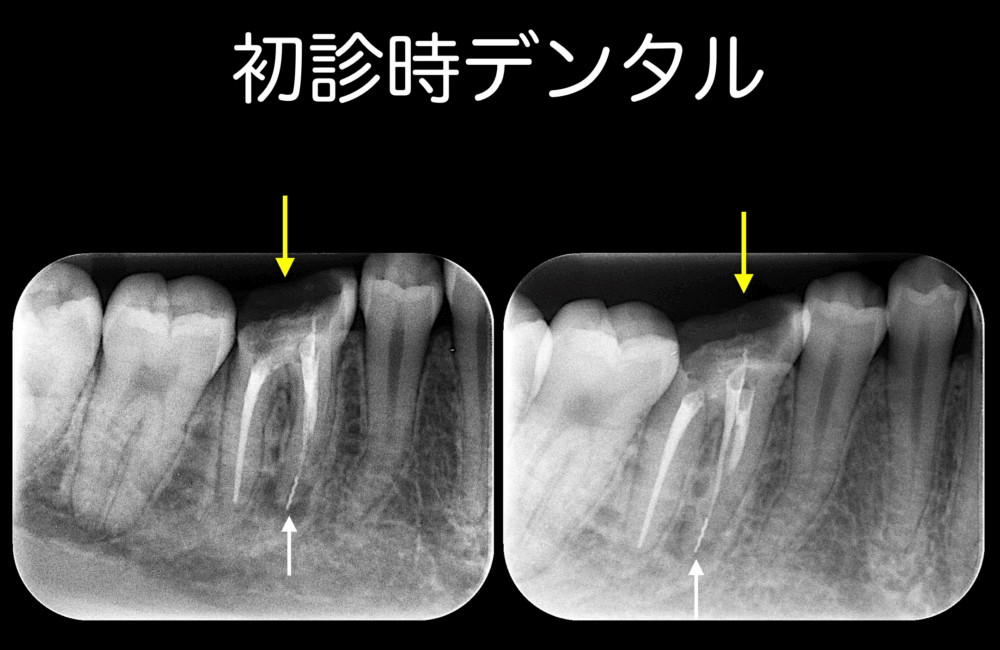

いつもももこ歯科のブログを読んでいただきまして、ありがとうございます。 今日のお話は、根管治療後のかぶせ物についてです。 根管治療が適応になる歯は、虫歯で崩壊していることが多く、強度的に弱くなります。 そこで、樽のタガの...